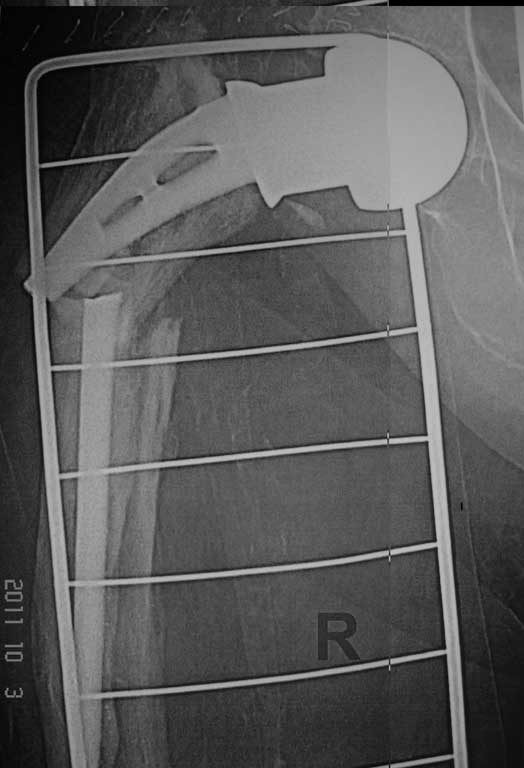

Добрый вечер. Уважаемые коллеги, впервые столкнулись с перипротезным переломом правой бедренной кости. Если есть опыт и идеи пожалуйста выскажите по поводу данного случая.

Женщина 86 лет, оперирована нами 6 лет назад по поводу перелома шейки правой бедренной кости . Травма двое суток назад - падение в квартире.Наши мысли по поводу данного случая - удаление протеза сломанной ножки и замена ревизионной цементной ножкой и модульной головкой , при этом не выполнять вскрытие кортикальной стенки в виде окна, для того чтобы убрать остатки цемента ,т.к эта процедура увеличит интраоперационную травму и кровопотерю, а с помощью рашпилей разработать канал, ввести в дистальный отломок цемент и посадить ножку,если будет нужно наложить серкляжные швы.

А были ли симптомы нестабильности протеза до травмы? Падение вряд ли могло быть причиной перелома ножки. По представленному снимку понять, есть ли нестабильность трудно. В любом случае, удаление даже нестабильного протеза без широкого вскрытия ложа может оказаться непреодолимой задачей и расчитывать на то, что это наверняка получится, не стоит. А если один из фрагментов фиксирован стабильно, то и с широким вскрытием канала задача может оказаться не из легких. Другое дело, нужна ли ревизионная ножка если Вы думаете о цементной фиксации? Если не заморачиваться обязательным сращением перелома и подумать о том, чтобы дать пациентке возможность какое то время относительно безболезненно походить с помощью ходунков, то можно поставить любую дешевую цементную ножку, даже из ранее удаленных у других пациентов. Можно и однополюсную.

На месте хирургов в этой ситуации я себя очень хорошо представляю. Перелом ножки происходит на фоне нестабильности, которая, в свою очередь, означает резкое истончение стенок костного канала и регионарный остеопороз на фоне и без того выраженного диффузного остеопороза. Расчитывать на стабильную фиксацию подвертельного перелома пластиной за тонюсенькие стенки при сохранении в канале отломков нестабильного эндопротеза...

А Вы это делали при перипротезных переломах, или при переломах ножки протеза, как в данном случае? здесь скорее транспротезный перелом, а не

перипротезный, и возникнуть от мог только при выраженной нестабильности ножки. Поэтому ревизионное протезирование длинной ногой единственно возможный вариант.